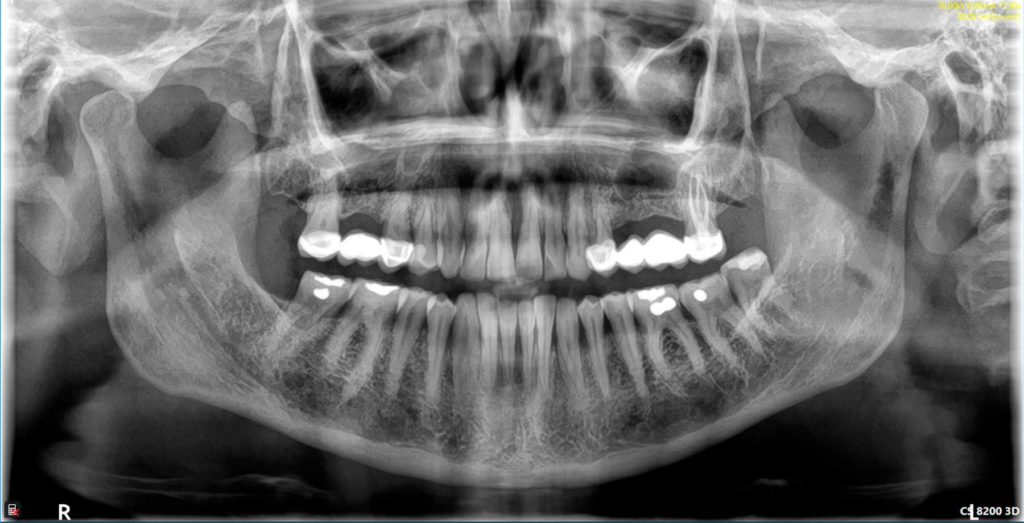

Radiología digital

Reduce en un 80% la radiación que recibe el paciente y permite obtener una imagen de forma instantánea, sin necesidad de revelado. Además, la tecnología digital permite la mejora de la imagen mediante técnicas informáticas. Hemos incorporado además, tecnología 3D mediante un sistema avanzado de Tomografía Computarizada de baja radiación CBCT (la de más baja radiación disponible en el mercado), lo que nos permite determinar la posibilidad de colocación de implantes en la primera visita diagnóstica, así como la detección de patologías asociadas a los maxilares.